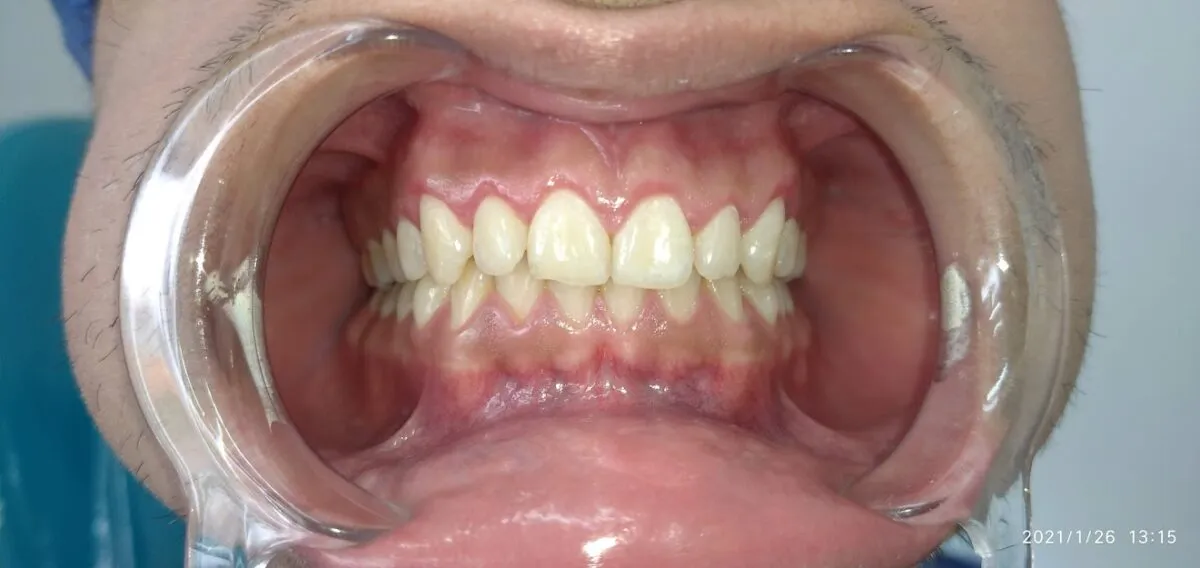

In this article we will show you a case of gingivectomy from before, during and after

After the gingivectomy, you have to wait a minimum recovery and healing time, which is usually two weeks.